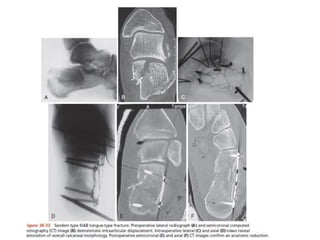

Fractura de calcaneo